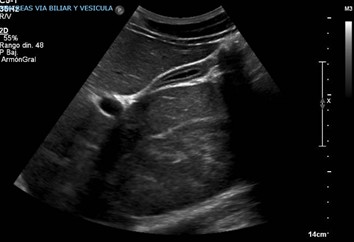

Se trata de un hombre de 27 años, natural y residente en Medellín, sin antecedentes relevantes desde el punto de vista médico. Consultó a urgencias de un hospital de alta complejidad por cuadro clínico de 3 semanas de evolución de fatiga, ictericia y deposiciones diarreicas. La presión arterial al ingreso era de 150/90 mm/Hg, la frecuencia cardiaca de 110 latidos por minuto, la temperatura de 36 ºC y la frecuencia respiratoria de 18 por minuto con un peso de 85 kilos, su estatura era de 190 cm y su IMC de 23.5. En la anamnesis reportó automedicación con Ligandrol tabletas de 25 mg, de las cuales se tomaba 50 mg diarios, con el objetivo de aumentar la masa muscular, cuatro semanas antes que dieran inicio los síntomas; se indagó por otros medicamentos, el paciente negó ingesta de otros medicamentos o suplementos. En los estudios iniciales (Tabla 1) se realizó un perfil de autoinmunidad (anticuerpos antinucleares) y se descartaron otras etiologías de hepatopatía, como las infecciosas entre las que están las hepatitis A, B y C, la sífilis y el VIH. Para descartar otras etiologías obstructivas se realizó una ecografía de hígado y vías biliares, sin evidenciar cambios inflamatorios (Figura 1.) Se pidió un electrocardiograma para descartar compromiso cardiovascular el cual no reportó hallazgos anormales se solicitó hemoleucograma al inicio, encontrando valores normales. Se anexan los resultados en la Tabla 1.

Nota: imagen de la ultrasonografía de hígado y vías biliares donde no se evidencian cambios inflamatorios, alteraciones en la ecogenicidad que sugieran lesiones infiltrativas y la vía biliar no se ve dilatada.

Las pruebas de imagen, como la ecografía abdominal, pueden ayudar a descartar otras causas de obstrucción biliar; sin embargo, en algunas ocasiones es necesario realizar imágenes más especializadas, como la colangiorresonancia. En este caso la ecografía descartó una alteración estructural, por lo que es importante realizar diagnósticos diferenciales, entre ellos, de infecciones por hepatotropos, causas metabólicas, autoinmunitarias y otras sustancias11,12,13.